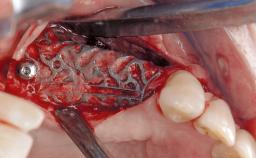

In this case, Myroslav Solonko, Ignacio Sanz Sánchez and Mariano Sanz present a treatment that aims to eliminate exposed implant threads by modifying the implant surface, converting a moderately-rough surface into a smooth surface.

A 63-year-old male patient was referred to the post-graduate periodontal clinic of the Complutense University of Madrid for the treatment of peri-implantitis. According to the patient’s record, all his maxillary teeth had been extracted ten years previously due to severe periodontitis, and a full-mouth implant-supported restoration on eight implants was placed. No supportive periodontal therapy was provided apart from occasional check-ups by the restorative dentist.